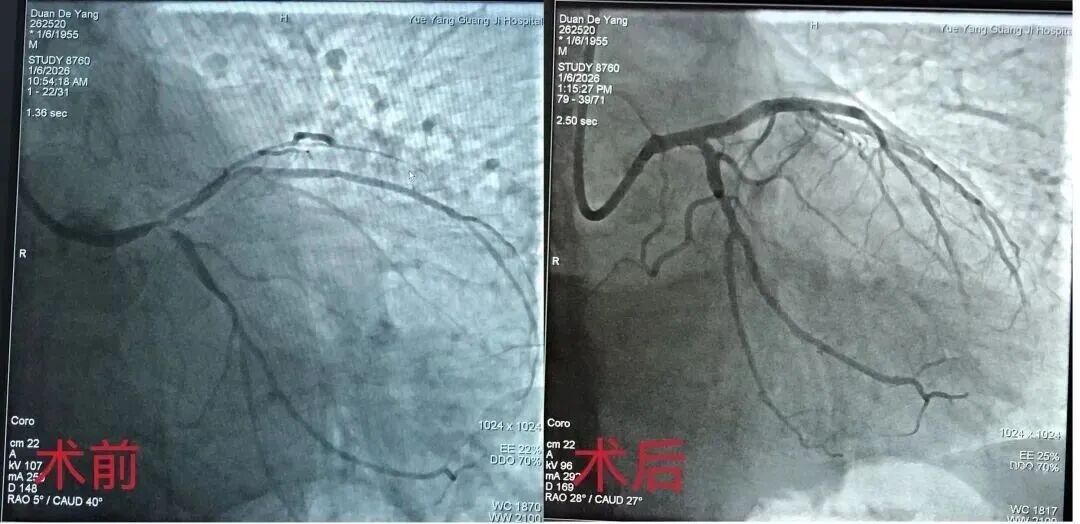

该患者确诊为严重左主干真性分叉病变、前降支重度狭窄伴钙化病变,血管解剖结构复杂,手术操作难度大、风险系数高,对诊疗团队的技术水平、方案制定能力和应急处置能力均提出了极高要求。

在杨模国主任的带领下,介入团队术前反复研讨病情、精准评估血管条件,制定了个性化手术方案。术中,在导管室医护人员的严密监护与配合下,团队精准运用冠脉血管内超声、切割球囊扩张成形术,联合多次导丝穿支架网眼、双球囊对吻扩张等多项复杂核心技术,对病变血管进行充分预处理后,成功完成支架精准植入,整个手术过程顺利有序。